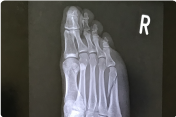

骨折

一口に骨が折れると言っても、引き起こされる症状は様々です。腫れや疼痛はもちろん、発熱、変形などを併発することもあります。また、高年齢の方はほんのちょっとした日常的な動作によって、成長期の10~15歳頃には瞬発的な運動によっても剥離骨折を起こすことがあります。

レントゲンの最新デジタル画像によって、小さな骨折や微妙な圧迫骨折も逃さなく診断できます。